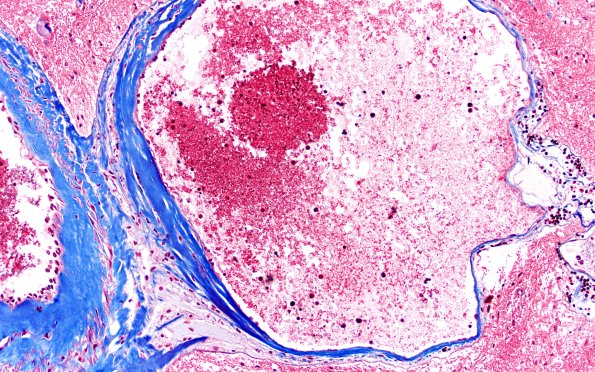

34E5 AVM, hybrid vessels (Case 34) TRI 20x 3

Higher magnification of image #34E4. (Trichrome)